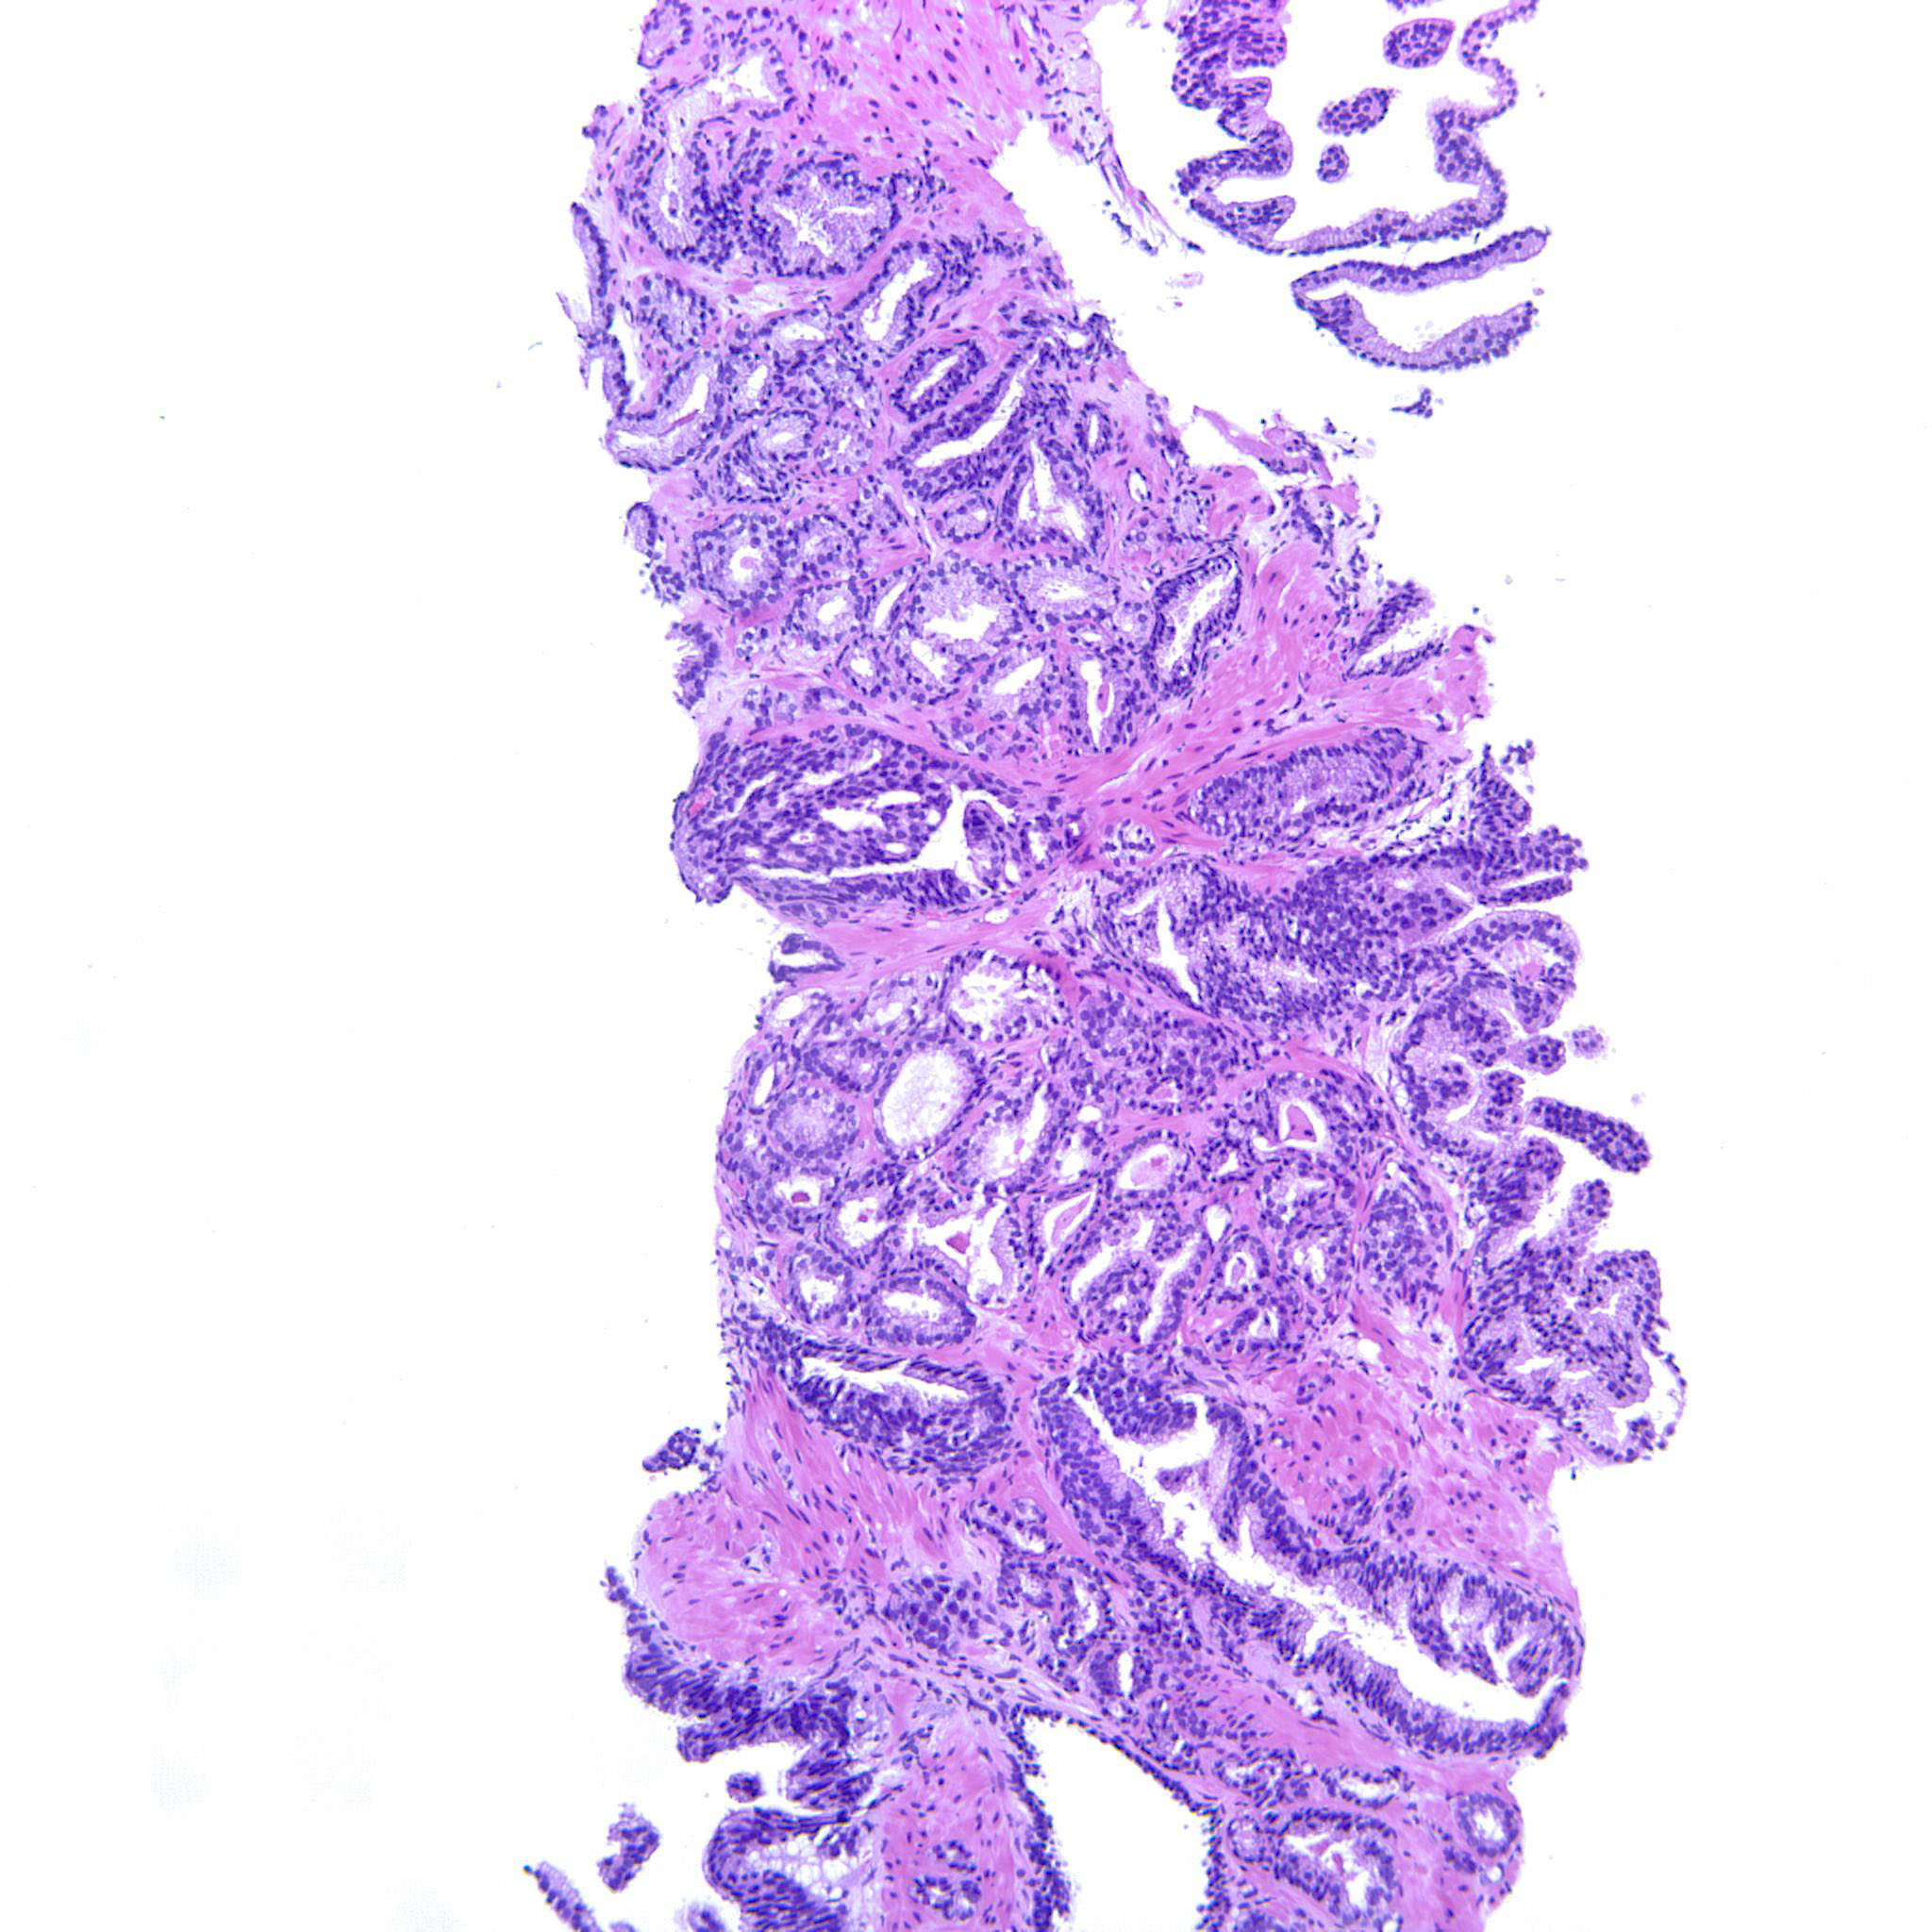

Prostate cancer grading

Case ID: 752